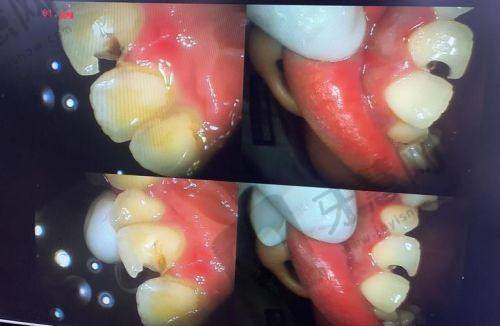

1. 即刻种植修复:该技术可以在拔牙后立即植入种植体,减少患者的就诊次数和等待时间,缩短疗程。同时,能更好地保存牙槽骨的高度和宽度,提高种植的成功几率和美观度。